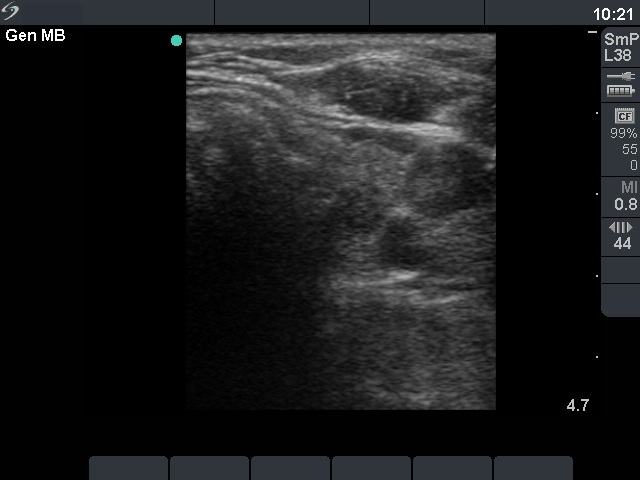

The role of complex diagnosis - follow-up of follicular lesions - Case 8. (ultrasonographic picture 5)

Left lobe, horizontal scan. There is a small moderately hypoechogenic lesion in the central part.